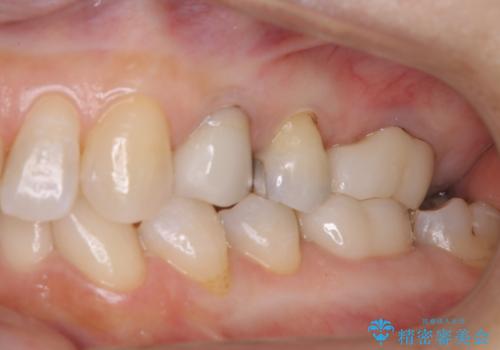

大好きなブラックコーヒーによる歯の着色を綺麗にしたい

- 大好きなブラックコーヒーを毎日飲むため、歯の着色がとても気になる。歯磨きでは取れないため綺麗にして欲しいとのことで来院されました。

PMTC60分コースを行いました。

毎日丁寧に歯磨きをしていても、日常生活での飲食物などにより着色してしまうことはあります。PMTCでは、歯の表面の凸凹にミネラルを補給して、ツルツルの表面に仕上げます。定期的にPMTCを行うことにより、歯質の強化になり着色がつきにくい状態になります。